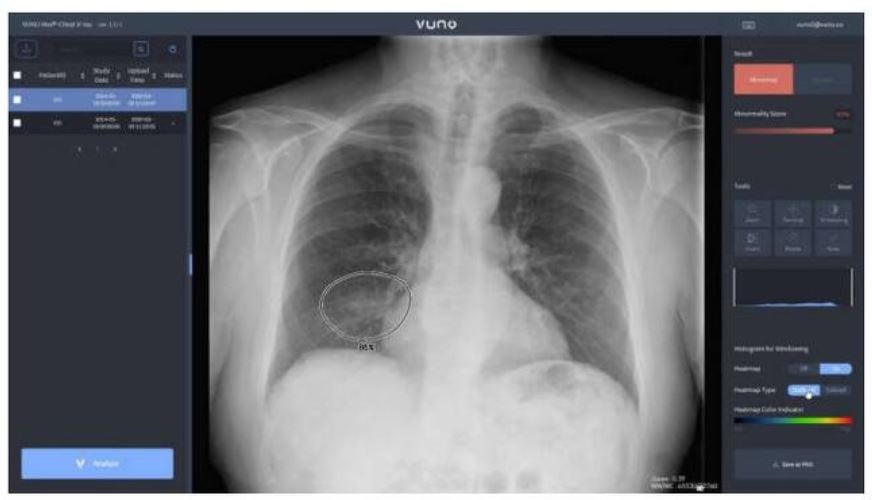

이에앞서 코로나19 진원지인 우한 시내 중난병원 등 34개 의료기관은 중국 현지 스타트업 인퍼비전이 개발한 AI기반 CT 판독 프로그램으로 3만2000건의 의심환자를 발견했다. 국내에서도 뷰노와 JLK인스팩션 등 의료 IT기업들이 확진자의 흉부 X레이 영상을 AI로 수초내로 판독해 중증환자를 분류하는 기술을 각각 홍천군과 대구지역 등 지역병원들에 제공하고 있다.